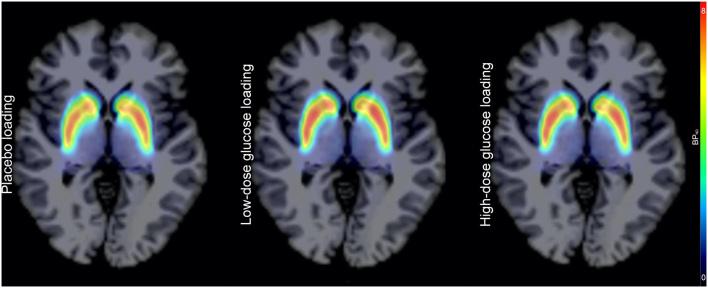

Brain dopamine neurotransmission is regulated by the dopamine transporter (DAT), which drives reuptake of extracellular dopamine into the presynaptic neurons. We hypothesized that the glucose loading dose would affect the striatal DAT availability. An i.v. bolus injection of 18F-FP-CIT was administered after infusion of low-dose glucose (300 mg/kg), high-dose glucose (600 mg/kg) or placebo (normal saline). The emission data were acquired over 90 min in 23 healthy male subjects. Substantial increases of binding potential (BPNDs) from ventral striatum (VST), caudate nucleus, and putamen were observed after low-dose glucose loading (+26.0, +87.0, and +37.8%) and after high-dose glucose loading (+10.4, +51.9, and +22.0%). BPNDs of the caudate nucleus and putamen showed significant differences (P = 0.0472 and 0.0221) after placebo, low-dose glucose, and high-dose glucose loading. BPNDs in the caudate nucleus and putamen after placebo, low-dose glucose, and high-dose glucose loading were positively intercorrelated with each other. In conclusion, striatal DAT changes after physiological glucose loading, but not after supraphysiological glucose loading in humans. DAT availabilities after placebo, low-dose glucose, high-dose glucose loading were correlated to each other in the caudate nucleus and putamen, but not in the VST. Therefore, sub-regional variability in DAT regulatory mechanisms mediated by insulin may exist in humans.

脑多巴胺神经传递受多巴胺转运体(DAT)调节,DAT驱动细胞外多巴胺重新摄取到突触前神经元中。我们推测葡萄糖负荷剂量会影响纹状体DAT的可用性。在输注低剂量葡萄糖(300mg/kg)、高剂量葡萄糖(600mg/kg)或安慰剂(生理盐水)后,静脉推注18F-FP-CIT。在23名健康男性受试者中采集了90分钟的发射数据。低剂量葡萄糖负荷(分别增加26.0%、87.0%和37.8%)和高剂量葡萄糖负荷(分别增加10.4%、51.9%和22.0%)后,观察到腹侧纹状体(VST)、尾状核和壳核的结合潜能(BPNDs)显著增加。安慰剂、低剂量葡萄糖和高剂量葡萄糖负荷后,尾状核和壳核的BPNDs存在显著差异(P = 0.0472和0.0221)。安慰剂、低剂量葡萄糖和高剂量葡萄糖负荷后,尾状核和壳核的BPNDs彼此呈正相关。总之,在人体中,生理性葡萄糖负荷后纹状体DAT发生变化,而超生理性葡萄糖负荷后则无变化。安慰剂、低剂量葡萄糖和高剂量葡萄糖负荷后,尾状核和壳核的DAT可用性彼此相关,但在VST中不相关。因此,人类可能存在胰岛素介导的DAT调节机制的亚区域变异性。